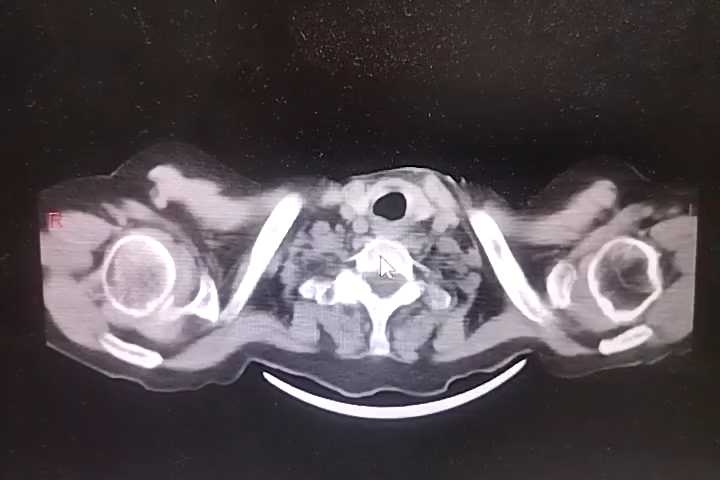

胸部+全腹部CT结果回报:双肺支气管炎,通气不良,双肺底多发索条,考虑1、膨胀不良2、慢性炎症,左肺下叶钙化灶,主动脉钙化,食管裂孔疝,纵隔多发淋巴结,肝门区钙化灶,胆囊密度低密度增高,考虑胆汁淤积,右肾囊肿?建议强化,双肾盂、输尿管扩张,膀胱过度充盈,考虑尿潴留,结合临床,直肠积粪密切观察病情变化。